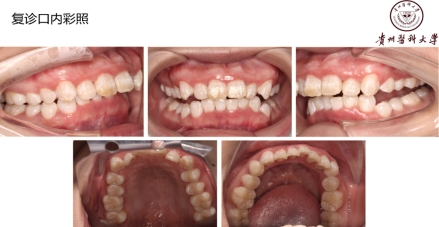

18岁,男性,经常抽烟,熬夜打游戏!!!

好发人群以及典型症状:该病好发于青壮年,多见于男性吸烟者、经常熬夜者、精神压力大者。得了这个病的话,前面描述的症状都可能会发生!牙龈的边缘及牙龈乳头发生坏死,常有黄白色假膜覆盖,很痛,有腐败臭味!!但是有这些症状时还是要小心另外一些很严重的疾病哦,比如白血病、艾滋等,得排除了它们,才能放心点。